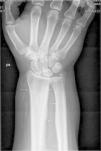

Hombre de 45 años, que es remitido a la consulta de Reumatología por dolores articulares difusos en muñecas y rodillas. El paciente está diagnosticado de cirrosis hepática con hepatocarcinoma y síndrome hepatopulmonar grave. En la exploración física presenta tumefacción de rodillas y muñecas (artritis) y acropaquias. En el estudio radiológico convencional solicitado se observa un engrosamiento perióstico continuo, grosero y ondulante, en localización diafisometafisaria de cúbito y radio en ambos antebrazos y de predominio en fémures distales en ambas rodillas, compatible con reacción perióstica no agresiva. En la figura 1 se observa el engrosamiento perióstico en ambos fémures afectando el borde cóncavo del hueso y respetando las epífisis, e igual afectación de cúbito y radio en la muñeca derecha, en la figura 2.

Los hallazgos a la exploración física de acropaquias –dedos en palillo de tambor– y artritis con tumefacción en manos y rodillas, así como la presencia en la radiografía de una periostitis continua de apariencia no agresiva afectando al borde cóncavo de los huesos largos tanto de las extremidades superiores como de las inferiores permitió establecer el diagnóstico de osteoartropatía hipertrófica. Esta entidad clínica se asocia fundamentalmente a procesos intratorácicos (sobre todo neoplásicos, especialmente el carcinoma broncogénico y tumores pleurales), aunque también a otras patologías entre las cuales se incluye la enfermedad hepática (hepatocarcinoma, hepatitis alcohólicas y la cirrosis hepática, tanto biliar como portal)1–3.